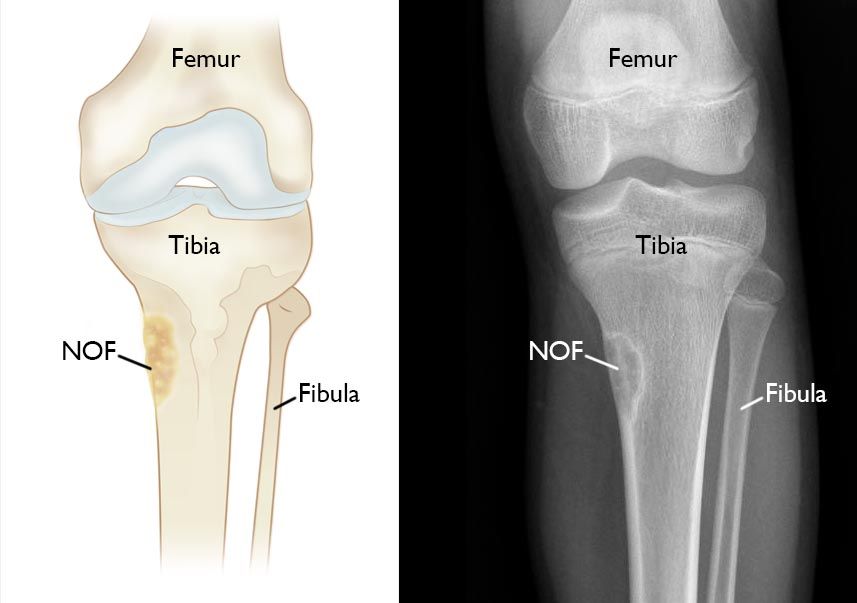

x-ray and illustration of NOF in tibia

Illustration and X-ray show an NOF at the upper end of the tibia (shinbone) near the knee joint. This is a common location for the tumors to occur.

Nonossifying fibromas are made of fibrous tissue and are typically yellow or brown in color. They most often occur in the flared end of the lower femur (thighbone) and in the flared upper or lower ends of the tibia (shinbone). NOFs also sometimes occur in the fibula (the smaller bone in the lower leg) and in the humerus (upper arm bone).